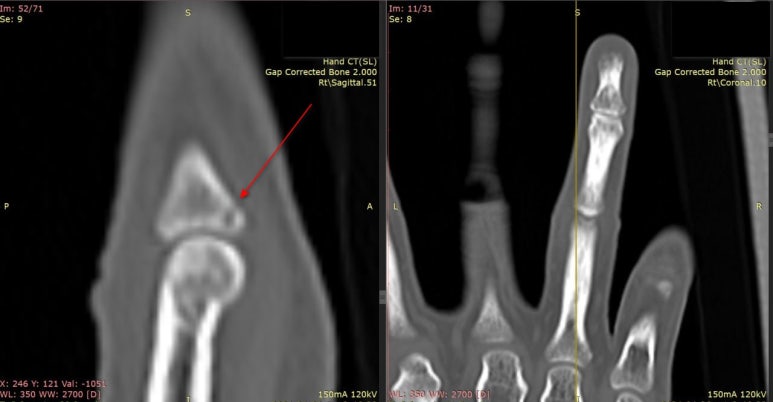

손가락 미세골절 최종 확진을 위해

협력병원으로 컨설트하여

CT 검사를 진행했습니다.

CT 검사상 급성 골절 확인

미세골절은일반 CT 단층 촬영에서도안 보이는 경우가 많습니다.

그래서 좀 더 촘촘하게 검사하는

로

확인하는게 좋습니다.

위 환자분은

640 CT 결과

로확진되셨습니다.

참고로 이 부위는

손가락이 과도하게 꺾이는 걸 막아주는

장측판(volar plate)이 손상되면서

뼈 조각이 떨어져나가는

이

잘 생기는 곳입니다.